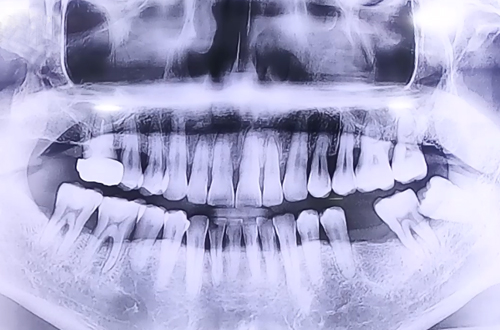

BEFORE

맨 앞쪽 발치 후 오랜 기간이 지난 큰 어금니와 앞쪽으로 기울여져 있으며 염증이 심한 사랑니,

그로 인해 심한 충치와 염증으로 흔들림이 많았던 사랑니 앞쪽 어금니로 자연 식립과 즉시 식립이 동시에 이루어진 환자분이십니다.

맨 앞쪽에 발치 후 오랜 기간이 지난 큰 어금니 부위에는 자연 식립 임플란트를 진행해 드렸고

사랑니와 그로 인해 흔들림이 심했던 큰 어금니를 둘 다 발치한 뒤에 원래 있어야 하는 자리에

뼈이식과 임플란트를 동시에 진행하며 반듯하게 심어 뚜껑을 덮어 마무리해 드렸습니다.